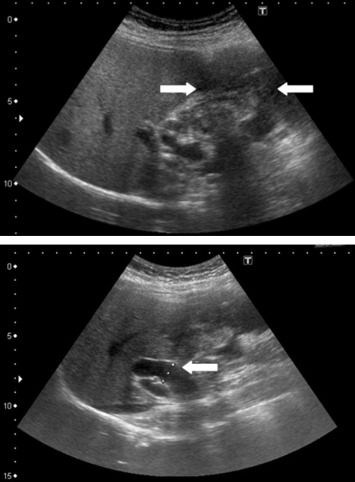

Cholecystectomy and segmental hepatectomy of segments S4b and S5 were performed. An 8 cm, friable gallbladder mass had grown outward and involved the liver (Fig. 3). Pathologically, the tumor was a sarcomatoid carcinoma in Stage III (Fig. 4). The surgical margin was free of vessel or cystic duct invasion. The tumor had an adenocarcinoma component with some glandular structures and showed positive staining for cytokeratin (AE1/AE3) and a sarcoma component with spindle cells staining positively for vimentin.

An 8 cm friable mass extending outward from the gallbladder and involving the ...

Figure 3.

An 8 cm friable mass extending outward from the gallbladder and involving the liver.